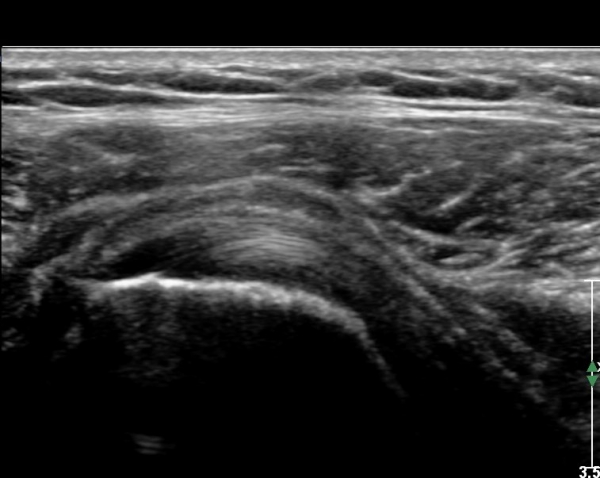

ŽÃËÀÚ¸¦ Á»´õ ¸»´ÜÀ¸·Î À̵¿ ÈÄ(¶Ç´Â ¾Æ·¡·Î ±â¿ïÀÎ ÈÄ) ³»ÃøºÎ¸¦ Á¶ÀýÇÏ´Ï °ß°©ÇÏ±Ù°Ç Ç¥ÃþÀ¸·Î Á¡¾×³¶³» ¼ö¾×Àú·ù°¡ °üÂûµÈ´Ù(»çÁö 3, 4). ŽÃËÀÚ¸¦ Á¶Á¤ÇÏ´Ï ÀÌµÎ¹Ú°Ç ÁÖÀ§ ¼ö¾× Àú·ù¿Í Á¡¾×³¶³» ¼ö¾×Àú·ù°¡ °üÂûµÇ¾î Á¡¾×³¶¿°°ú Ȱ¾×¸·¿°ÀÌ ÀÖÀ½À» ¾Ë ¼ö ÀÖ´Ù(»çÁø 5).